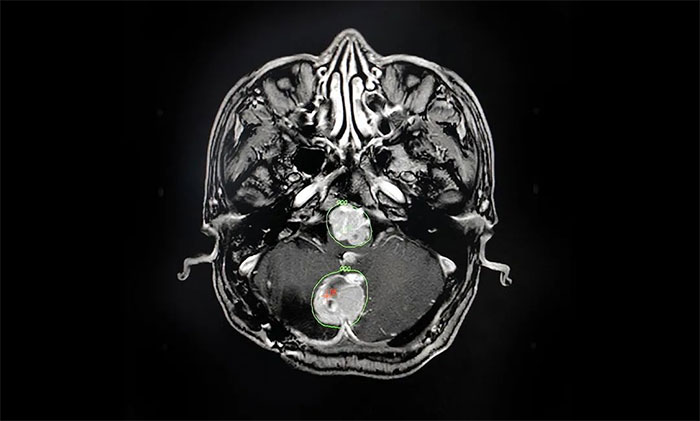

入院后,腫瘤科(放療)頭部伽瑪?shù)督M主任陳琦為他完善了MRI檢查,明確多處腫瘤的位置、體積(單體腫瘤最大直徑約2.7cm)。經(jīng)與神經(jīng)外科、醫(yī)學(xué)影像科等開展MDT多學(xué)科聯(lián)合會(huì)診,評(píng)估復(fù)發(fā)腫瘤病灶毗鄰腦干等重要功能區(qū),手術(shù)難度高、風(fēng)險(xiǎn)大,可通過頭部伽瑪?shù)吨委煟刂颇[瘤生長(zhǎng),快速緩解臨床癥狀。

▲ 科學(xué)制定伽瑪?shù)吨委熡?jì)劃

經(jīng)過詳細(xì)論證,擬定好個(gè)性化的治療方案后,陳琦主任將治療過程為患者及家屬進(jìn)行了詳細(xì)說明,并明確告知過程中可能存在的風(fēng)險(xiǎn)。在取得家屬一致同意、簽字確認(rèn)后,他立即投入術(shù)前的準(zhǔn)備工作中。